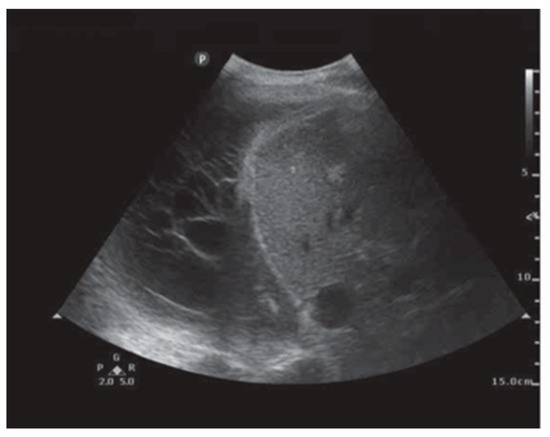

In addition to HRCT, there are several other imaging advancements very similar to the ones discussed in the lung cancer section that help in the diagnosis and monitoring of parenchymal lung diseases, including OCT, ultrasound, and PET. Earlier, we reviewed how OCT can be helpful for diagnosing lung nodules. Similarly, OCT offers minimally invasive high-resolution images for ILD diagnosis [20]. OCT has been shown to have sensitivity and specificity of 100% in detecting usual interstitial pneumonia patterns [21]. External validation and larger studies are required for clinical implementation. This could reduce reliance on surgical lung biopsy. Another form of imaging used includes ultrasound, which we have seen used for lung nodules as well. For parenchymal lung diseases, the pattern of abnormality is typically more diffuse. The radial ultrasound probe is inserted through a bronchoscope into the patient’s airways until it reaches the pleural surface. The probe is then slowly withdrawn from the pleura to the hilum, while examining the characteristics on the ultrasound image. This method helps determine a better location to biopsy. A dense sign correlates with a higher pathological confidence than a blizzard sign (Figure 3). Moreover, radial EBUS helps clinicians choose appropriate biopsy sites for cryobiopsy and identify blood vessels close to lesions, which should be avoided when a biopsy is performed. Minoru et al. demonstrated high-quality lung specimens with dense signs on radial EBUS while decreasing the bleeding risk [22]. Sarcoidosis is another common multisystemic disease characterized by the formation of non-caseating granulomas in various organ systems. Establishing the presence of inflammatory activity is crucial for diagnosis and the monitoring of treatment. One of the most common organs affected by sarcoidosis include the lungs. This condition affects the lungs in more than 90% of patients [23]. Sarcoidosis can affect the parenchyma, the mediastinal and hilar lymph nodes, or both. Increased FDG uptake in the pulmonary parenchyma is associated with inflammatory activity, presumably inflammatory cells, including activated macrophages, lymphocytes, and neutrophils, and, possibly, disease severity (Figure 4). One cannot solely rely on a PET scan for diagnosis and must use other forms of diagnosis, including history, physical examination, and serologic markers. It was found by Mostard et al. that 20% PET scans are positive without serological signs of inflammatory activity. PET can add value to the assessment of sarcoidosis and other inflammatory lung diseases in patients with symptoms despite the absence of serologic inflammatory markers [24]. Other patients do not exhibit parenchymal disease and just have mediastinal and hilar lymphadenopathy. In addition to PET scans, which can show hypermetabolic uptake in lymph nodes, ultrasound with linear EBUS can be used to examine the lymph node in real time and obtain tissue samples. Characteristics that can be examined include lymph node size, shape, margin, echogenicity, central hilar structure, and granular appearance (Figure 5). Furthermore, EBUS TBNA has shown a sensitivity of 89–100% and a specificity of 94–96% in diagnosing sarcoidosis [25]. This procedure and imaging technique can be used for diagnosing other thoracic diseases that infiltrate the mediastinal and hilar lymph nodes, such as infectious causes like TB or fungal infections, other inflammatory diseases like hypersensitivity pneumonitis and vasculitis, and malignant diseases.

Figure 3. (A) Normal lung, (B) dense sign, and (C) blizzard sign. The white arrow is a pulmonary artery. Reproduced from Inomata et al., 2020 [22]. Shared in accordance with the Creative Commons Attribution Non Commercial (CC BY-NC 4.0) license, which permits others to distribute, remix, adapt, build upon this work non-commercially, and license their derivative works on different terms, provided the original work is properly cited, appropriate credit is given, any changes made indicated, and the use is non-commercial. See: http://creativecommons.org/licenses/by-nc/4.0/.